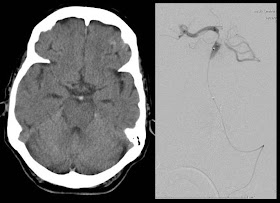

- Thrombotic basilar artery occlusion.

- MRI or CT angiogram - basilar artery occlusion, either in the proximal portion (top of the basilar syndrome, usually with midbrain and thalamic damage) or more extensively.